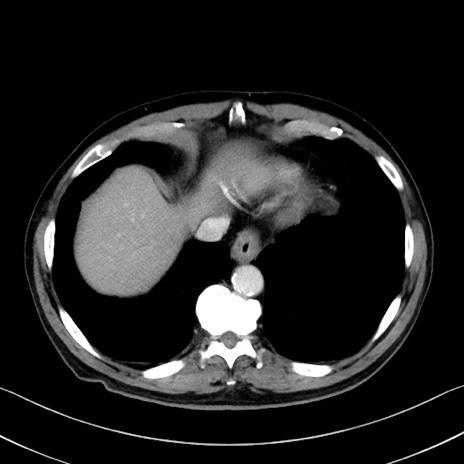

症例35(横断像)

【症例】70歳代 男性

【主訴】腹部膨満、嘔吐

【現病歴】昨日より腹部膨満感出現。本日増悪し、仙痛出現。嘔吐あり、受診。

【既往歴】糖尿病、胆摘後

【身体所見】BP 149/80mmHg、HR 74/min、BT 35.9℃、腹部:膨満、軟、圧痛なし。腸雑音減弱あり。上腹部正中切開瘢痕あり。

【データ】WBC 13500、CRP 1.72